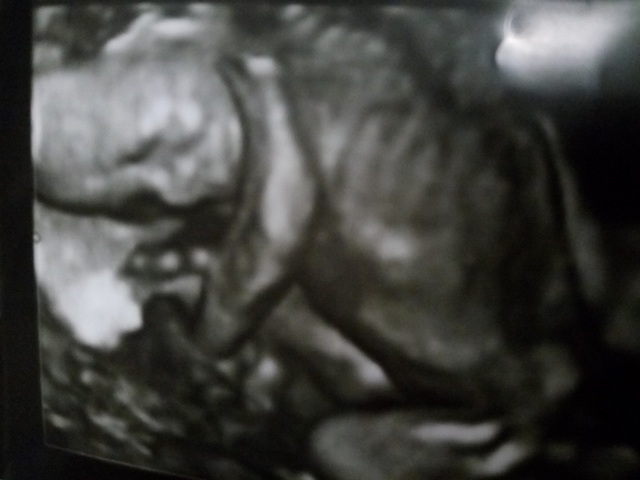

19週3日(19w3d・女の子)|すけろく さん(32歳)

エコー写真撮影時のエピソード:

だいぶお腹が大きくなってきて、服によっては妊婦さんとわかるようになってきた頃です。ムカムカしたり、日によって食べれるものが違ったり、食べ過ぎたりしていたつわりも少し収まって普通の食事ができるようになってきた頃で体調は落ち着いていました。お父さんはいつも検診に行っていましたが、いつも顔を見せてくれて嬉しそうでした!この頃から骨がしっかりしてきて肋骨が立派に見えるのがこの写真のお気に入りポイントです。

このしばらく後に転居し、4Dエコーをやってくれない病院になってしまったので顔がはっきり見られなくなって残念です。